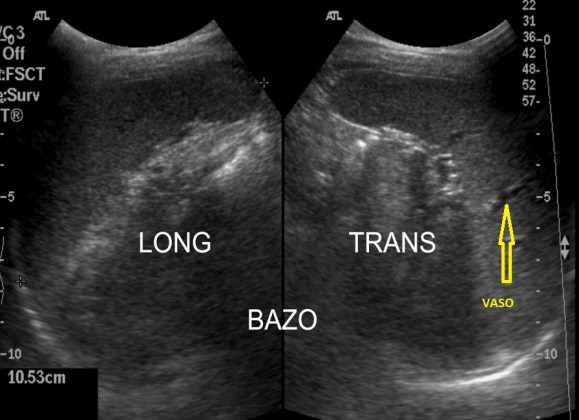

Ecográficamente es una estructura voluminosa, hiperecogénica y homogénea que no debe medir en adultos más de 12 cms. Los vasos de la estructura se verán anecoicos.

Semiología ecográfica.

Detalle del vaso.

Longitudinal con medidas. Observe el lector el pictograma.

Transverso. Detalle del pictograma en amarillo.

La estructura del Bazo hace que tanto en transverso como en longitudinal el Bazo aparece ecográficamente como una estructura que estuviese reflejada en un espejo. Mira:

En Long y en Trans como si la estructura estuviese reflejada.